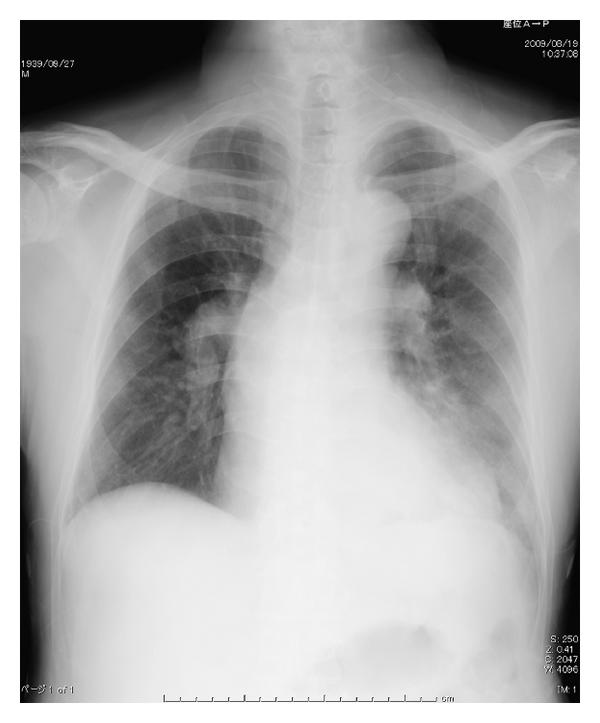

Initial PTPA was performed for his left pulmonary artery. Seven peripheral regions of his left pulmonary artery was dilated by the balloon. At the end of the procedure, his pulmonary artery pressure was 91/27 mmHg, and he was admitted to the intensive care unit. On admission to the intensive care unit (day 0), his SpO2 was 95% with 40% of oxygen inhalation with no complain of dyspnea. On day 1, his chest X-ray and computed tomography revealed localized consolidation on his left lower lobe (Figure 1). On day 2, consolidation on chest X-ray developed in accordance with his complication of dyspnea. Because his SpO2 decreased to 70% with 10 L/min of oxygen inhalation using reservoir mask, NPPV was applied.

(a)

(b)